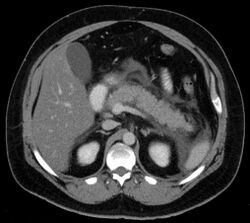

Acute exudative pancreatitis on CT scan

Calcified pancreatic duct stones with some free intra-abdominal fluid

A contrast-enhanced CT scan is usually performed more than 48 hours after the onset of pain to evaluate for pancreatic necrosis and extrapancreatic fluid as well as predict the severity of the disease. CT scanning earlier can be falsely reassuring.[citation needed]